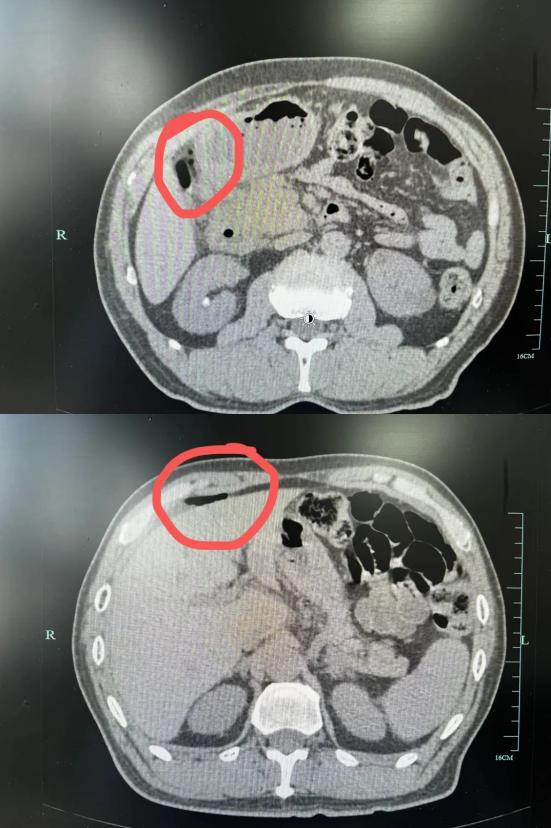

看到这种情况,当时值班的副主任徐超立即安排了王叔叔的检查,并根据病史安排了全腹部。 CT 检查。

根据 CT 检查结果显示,王叔叔腹腔内有明显的游离气体和液体聚集。结合王叔叔最近的生活习惯和临床表现,徐主任被诊断为消化道穿孔,情况比较危急,必须立即处理!

徐主任果断决定为王大伯实施“腹腔镜下腹部探测术” 穿孔修补”。术中发现,王大伯腹腔内有大量脓液,十二指肠降部有一个很大的穿孔炉,周围有疤痕性水肿。